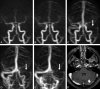

Fig 2.

Twenty-five-year-old man with subacute thrombosis (thrombus age, 4 days) of posterior portion of superior sagittal sinus, torcular region, and right lateral sinus. Sagittal source image of static VIBE part of combo-4D MRV reveals large isointense filling defect within posterior portion of superior sagittal sinus extending into torcular area (long white arrow in A). On sagittal whole-brain MIP reconstructed image of 2D TOF MRV, most of this thrombus shows hyperintense signal intensity mimicking flow. The small vertical signal intensity gap (short white arrow in B) was misinterpreted as artifact on a single section derived from in-plane signal intensity loss (coronal acquisition). No flow signal intensity is depicted in thrombosed right lateral sinus.

Fig 3.

Seventy-six-year-old man with acute venous thrombosis involving left parietal cortical vein (thrombus age approximately 1 day). GRE image shows typical magnetic susceptibility effect with hypointense signal intensity and blooming in left parasagittal parietal cortical vein (long white arrow in A). Static 3D contrast-enhanced VIBE MR venographic images from combo-4D MRV are centered on region of interest (B and C). No evidence of cortical venous filling defect can be seen on axial image (B) and targeted axial thick-slab MIP reformation (thickness, 20 mm; C) of VIBE sequence in corresponding area. Likewise, this thrombosed cortical vein is not evident on 2D TOF MR venogram, as demonstrated by targeted axial thick-slab (thickness, 20 mm; D) and standard coronal whole-head (E) MIP reformations. On the latter image, additional thrombosis of right lateral sinus is depicted (short white arrows in E).